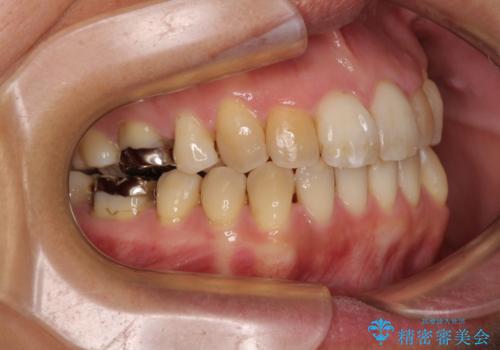

前歯の後戻り インビザラインでの再矯正治療

- かつて抜歯矯正を行ったものの、後戻りをしてしまったとのことで来院された患者様です。

上顎前歯が前突し、隣の歯が裏側に移動してきている状態でした。

飲み込みの状態を確認したところ、舌の突出癖が認められたため、それによる後戻りの可能性が高いと考え、舌のトレーニングを指導しました。

舌のトレーニングをしっかりと行ってくださり、10ヶ月で希望通りの歯列となりました。

日頃から飲まれる飲み物の影響で着色しやすいため、来院の度に着色除去のクリーニングも行っていました。